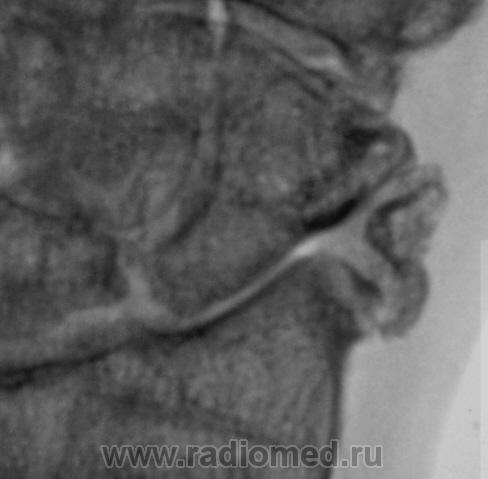

Пациент направлен в рентгеновский кабинет врачом хирургом для рентгенографии лучезапястного сустава. Пациент утверждает, что накануне, имела место быть травма. Произведена рентгенография в стандартных проекциях.

Можно сказать без свежих костно-травматических изменений, веротнее всего посттравматический деформирующий остеоартроз луче-запястного сустава 2ст.(по Н.С. Косинской), да и в межзапястно-пястном суставе так же дегенеративные изменения.

Застарелый отлом фрагмента от шиловидного отростка лучевой кости, деф. артроз л/з сустава.

Cогласен с последним постом.